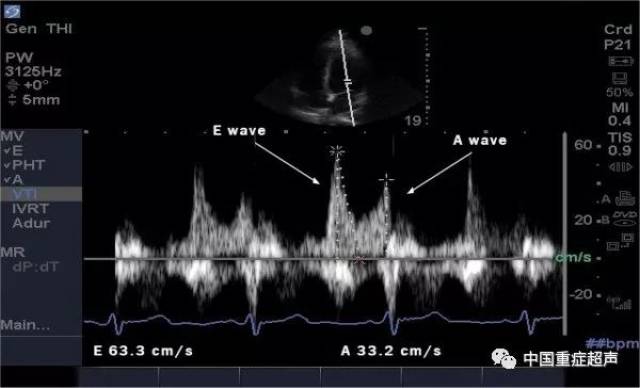

超声心动图E/A

分不清e峰和a峰怎么办